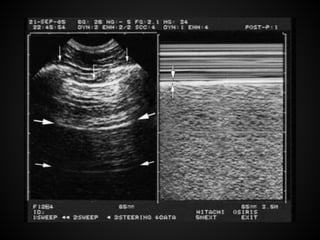

M mode: to examine structures that are in motion

such as the cardiac walls or the walls of the vena cava

Technique M mode: toexamine structures that are in motion such as the cardiac walls or the walls of the vena cava 1. Subcostal long axis (SLAX) 2. Subcostal inferior vena cava (SIVC) 3. Parasternal long axis (PLAX) 4. Parasternal short axis (PSAX) 5. Apical 4 chamber (A4CH)